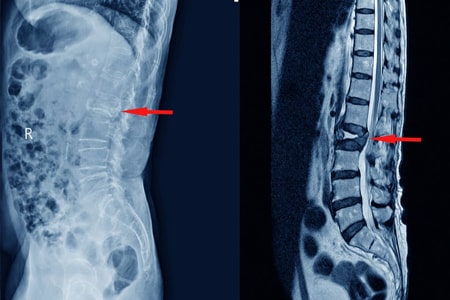

Tratamientos conservadores en el tratamiento de las fracturas vertebrales por compresión con dolor agudo : revisión sistemática y metanálisis en red

Los AINE y la teriparatida pueden ser las opciones de tratamiento preferidas para el tratamiento del dolor agudo en las fracturas vertebrales por compresión osteoporóticas. Aunque la calcitonina también demostró ser beneficiosa, su perfil de seguridad y los posibles efectos adversos restringen su aplicación generalizada. La evidencia limitada sobre los aparatos ortopédicos y los analgésicos subraya la necesidad urgente de investigaciones futuras. JAMA Netw Open. 3 de septiembre de 2024